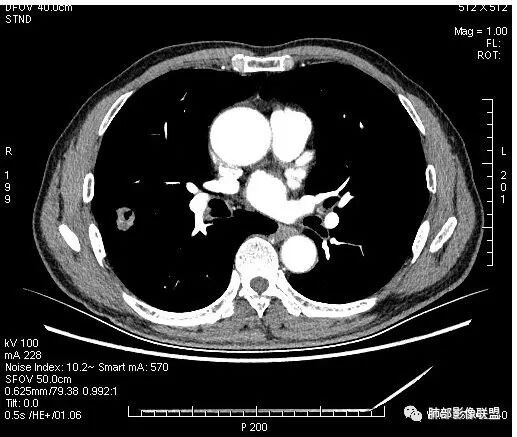

影像学改变:

1.右肺上叶后段类圆形结节影,密度不均,有坏死空洞,坏死比较彻底,内外壁都较清楚。

2.病灶有浅切迹,没有深分叶,毛刺大多细长且柔软。

3.可见棘状突起及胸膜牵拉,但未见胸膜凹陷。

什么意思?结节影有牵拉的动作,但似乎“出工不出力”,收缩力羸弱!

4.病灶轻到中度强化。病灶内血管走行较完好,病灶旁血管局部显示粗大。

5.支气管关系不确定。

6.灶周见小结节影(卫星灶),边界不甚清晰。